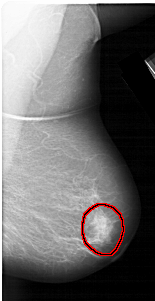

A_1309_1.RIGHT_MLO

RIGHT_MLO LINES 5716 PIXELS_PER_LINE 2941 BITS_PER_PIXEL 12 RESOLUTION 43.5 OVERLAY

FILE: A_1309_1.RIGHT_MLO.OVERLAY

TOTAL_ABNORMALITIES 1

ABNORMALITY 1

LESION_TYPE MASS SHAPE IRREGULAR MARGINS ILL_DEFINED

ASSESSMENT 4

SUBTLETY 4

PATHOLOGY BENIGN

TOTAL_OUTLINES 1

BOUNDARY